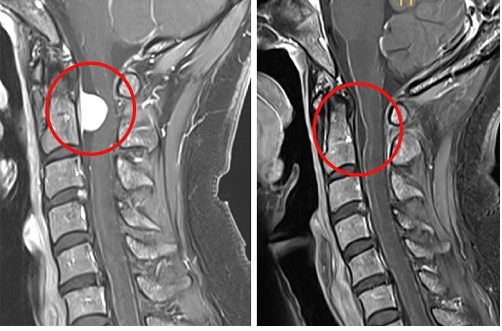

Professor Im Soo-bin explained, “The tumor was positioned in the posterior section of the medulla oblongata and spinal cord, ahead of the neurovascular structures. Employing the conventional approach of posterior midline access and laminectomy carried a significant risk of widespread paralysis, muscle weakness, and bleeding. Consequently, we had to explore alternative methods.” Professor Im Soo-bin devised a surgical plan involving access behind the ear and making an incision beside the dura mater surrounding the spinal cord, with the goal of minimizing disruption to the neurovascular structures. This approach resulted in minimal bleeding during the procedure, obviating the need for a transfusion, and enabled the complete removal of the spinal cord tumor without any subsequent paralysis.

2. (Left) Tumor located anterior to the upper cervical nerves before surgery (Right) Tumor completely removed after surgery